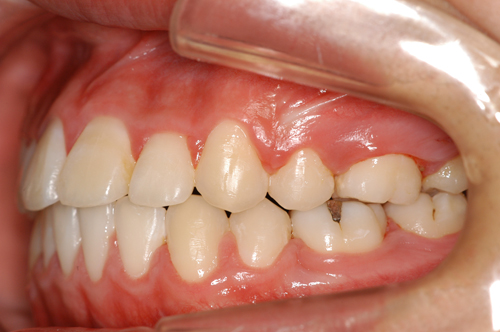

患者:14歳8ヶ月 男性

抜歯部位:上顎、第一小臼歯 下顎第二小臼歯

動的治療期間:18ヶ月